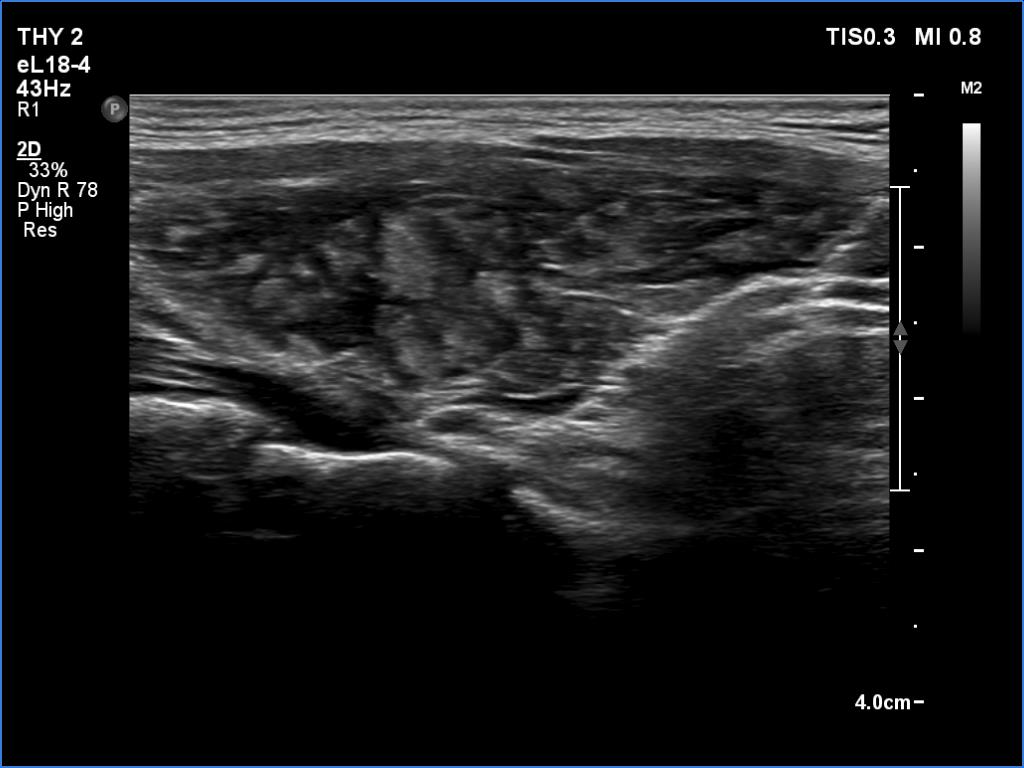

Ultrasonography. The thyroid was deeply hypoechoic and had numerous discrete iso/hyperechoic lesions. The latter had irregular shape and borders. The vascularity was increased. None of the discrete lesions corresponded to pathological nodules.